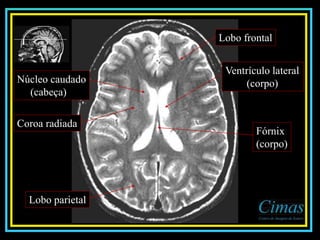

Lobo frontal

Ventrículo lateral

(corpo)

Coroa radiada

Núcleo caudado

(cabeça)

Fórnix

Lobo parietal